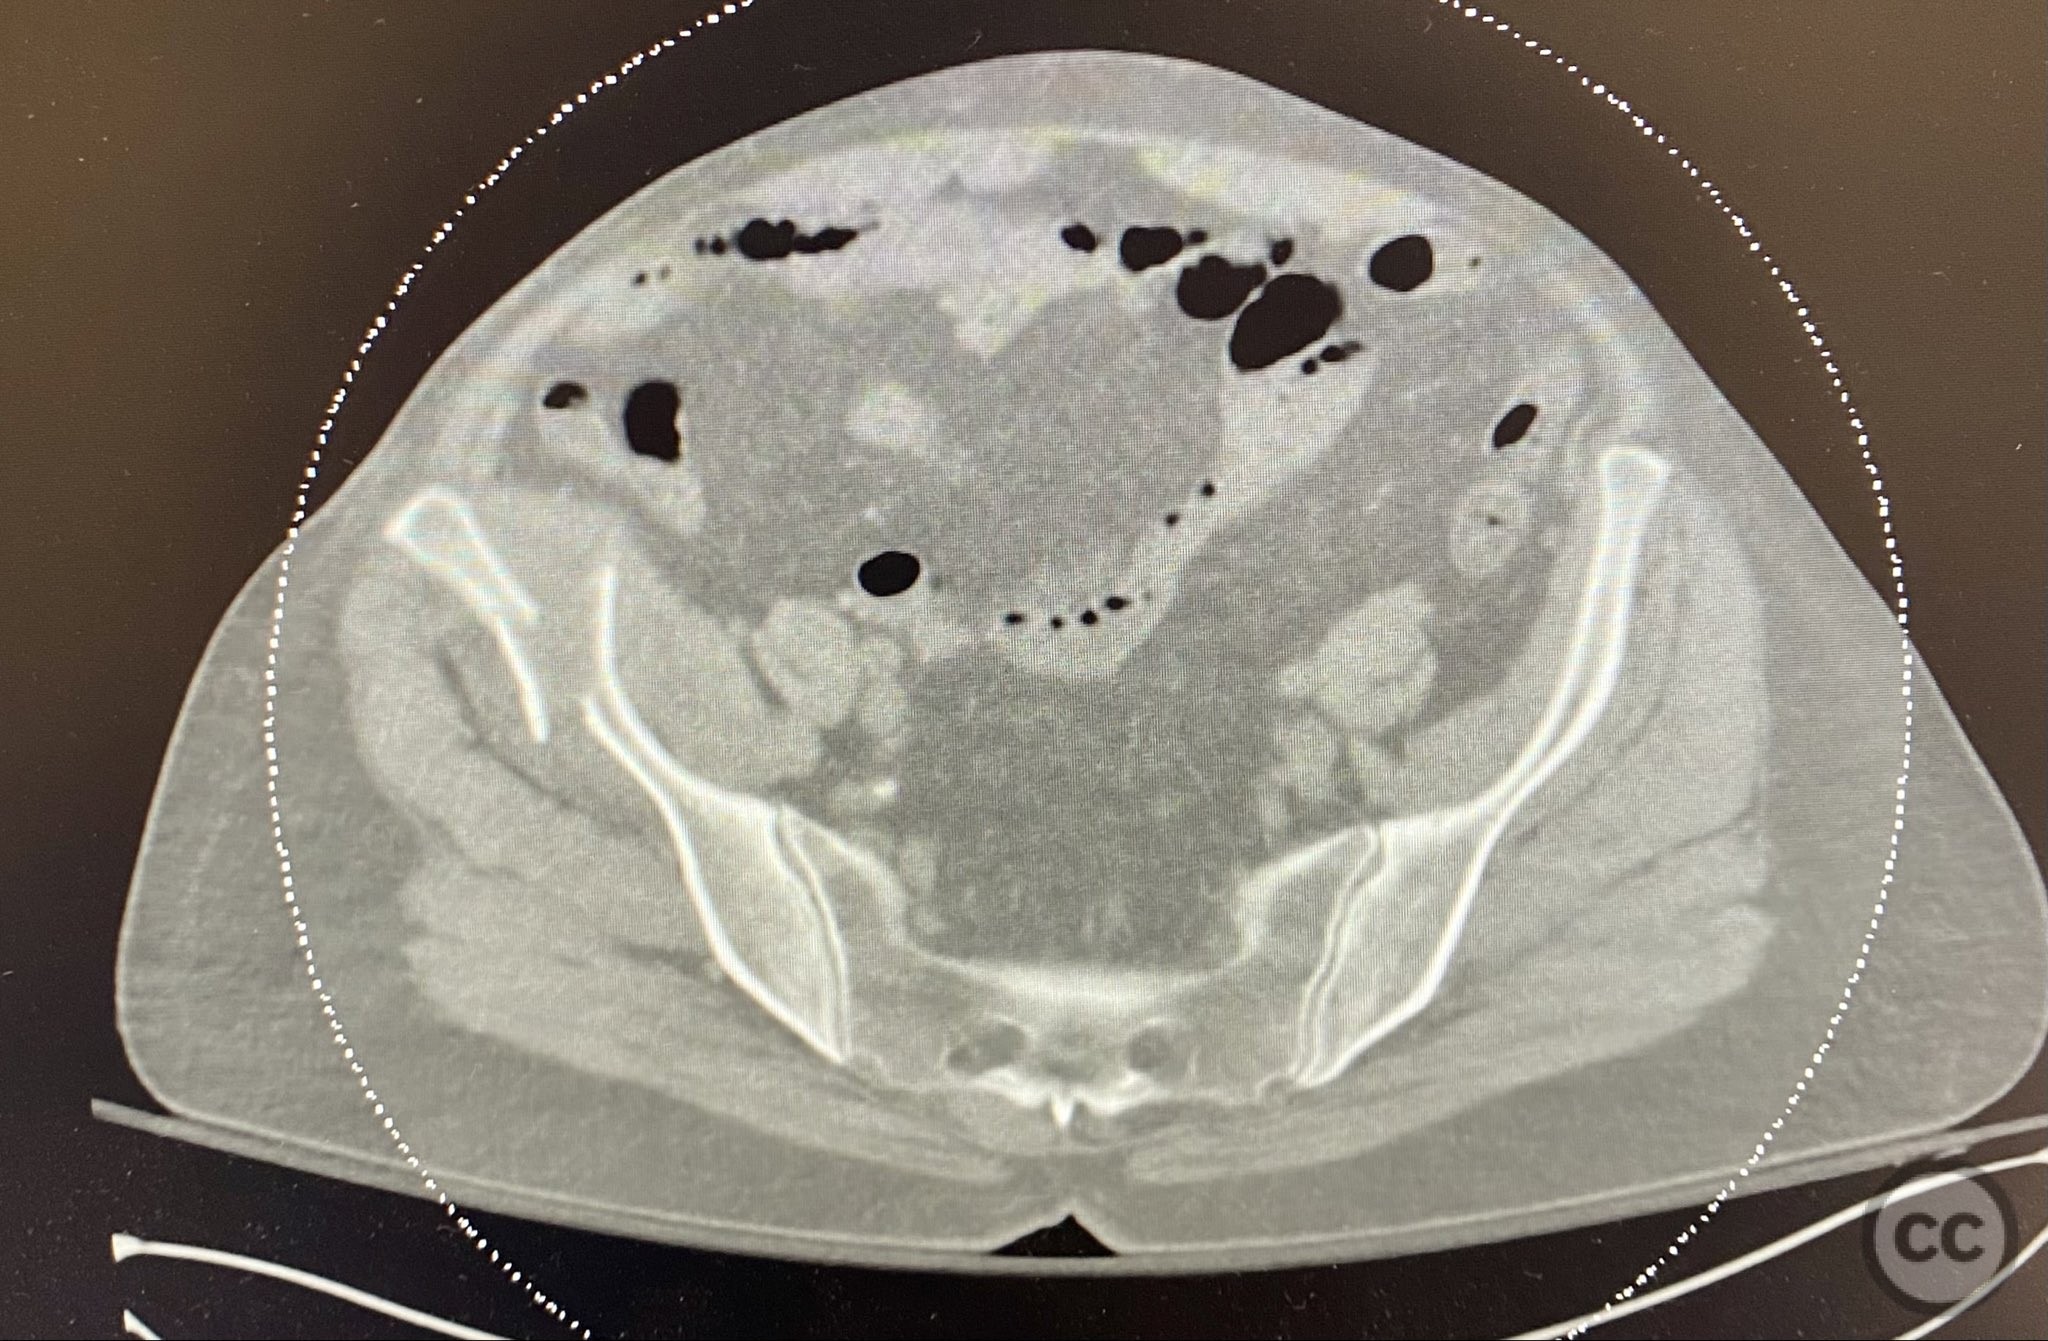

Clinical and radiological findings:  A middle-aged patient sustained a closed, displaced, and comminuted fracture of the right os ilium following a fall from height. Initial AP pelvic radiograph and 3D surface rendered imaging demonstrated significant comminution, displacement, and poor bone quality. The patient was unable to mobilize due to pain. No associated neurovascular deficit or additional pelvic ring injury was reported. AO/OTA classification: 61B2.2 (partial articular, comminuted iliac wing fracture).

Planning remarks:  The preoperative plan was for open reduction and internal fixation via an iliac approach, with extension medially as required for visualization. Reduction was to be achieved with direct manipulation and clamping, followed by lag screw fixation between the inner and outer iliac tables, and supplemental fixation with a contoured and tensioned plate.